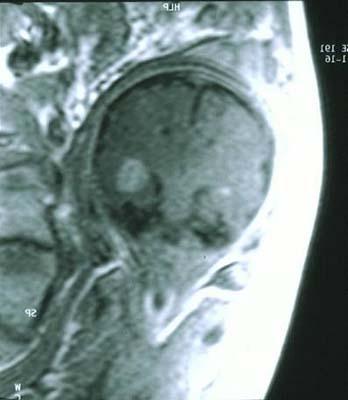

Rhabdomyome IRM